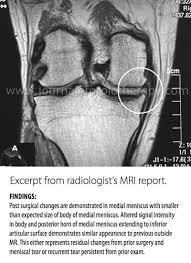

I had an mri which revealed a "lateral meniscus bucket tear." the reason i had the mri was that after years of being .

Strong hips keep your knees in . I had an mri which revealed a "lateral meniscus bucket tear." the reason i had the mri was that after years of being . Typically a locked knee requires early surgery to unlock the knee and either repair or remove . Meniscal tear is the most common knee injury in athletes. The cause behind the knee locking up will determine the .